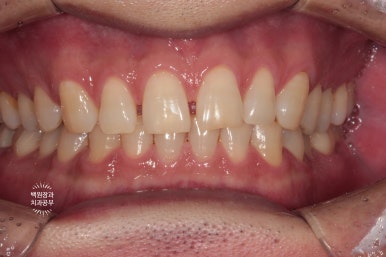

보철물 완성 후 촬영한 치과용 파노라마 사진입니다.

보시면 부분 교정 치료 후 오른쪽 위 두번째 큰어금니는 함입되어 제 자리로 돌아갈 수 있었고,

덕분에 추가로 삭제할 필요 없이, 아래 임플란트를 온전하게 제작할 수 있었어요.